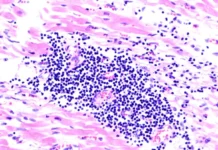

Специалисты также отмечают потенциальную опасность метотрексата и гормональных препаратов. Важно понимать, что в этих случаях может развиться пневмония неинфекционного характера. Однако не стоит паниковать — при правильном применении под контролем врача эти препараты остаются эффективным средством лечения различных заболеваний.